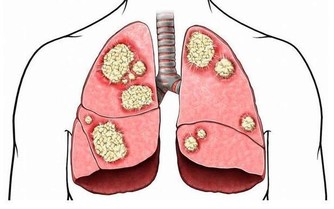

鼻子最常見的疾病有鼻出血、急性鼻炎、慢性鼻炎、鼻咽癌等。